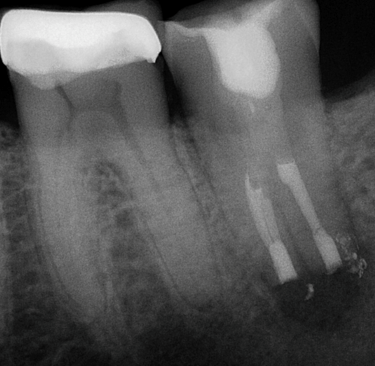

Thorough diagnostic testing and x-ray (radiographic) imaging will be completed to ensure an endodontic problem exists and if it’s the tooth with previous root canal treatment. Additionally, Cone Beam CT 3D imaging will be required to help identify the cause of failure, and to give exact and proper measurements needed for the procedure. Your medically history will also be thoroughly reviewed. The prognosis and description of intentional replantation will then be explained to you.

The tooth is then placed in a specialized solution to keep the roots and ligament hydrated. The small, infected portion of the roots are removed. Next, the root ends are prepared and filled with a specialized material, sealing the roots. These steps are completed efficiently and promptly, as working time needs to be kept to a minimum to prevent dehydration of the tooth and ligament, and thus achieve an optimal outcome.

The treated tooth is now placed back in the socket (replanted) in its original position. Sutures, or a splint, may be placed to keep the tooth in position. It is important to bite on gauze for the rest of the day to aid in keeping the tooth in the socket.

Treatment Completed by Dr. Battista